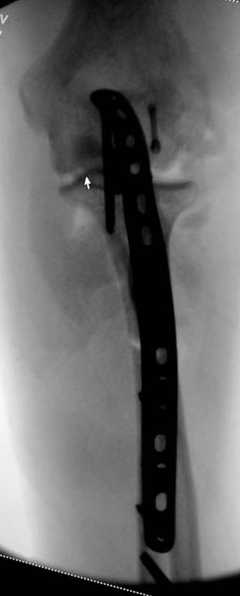

3 вариант

перелом с capitellum humerus и проксимальной трети улна